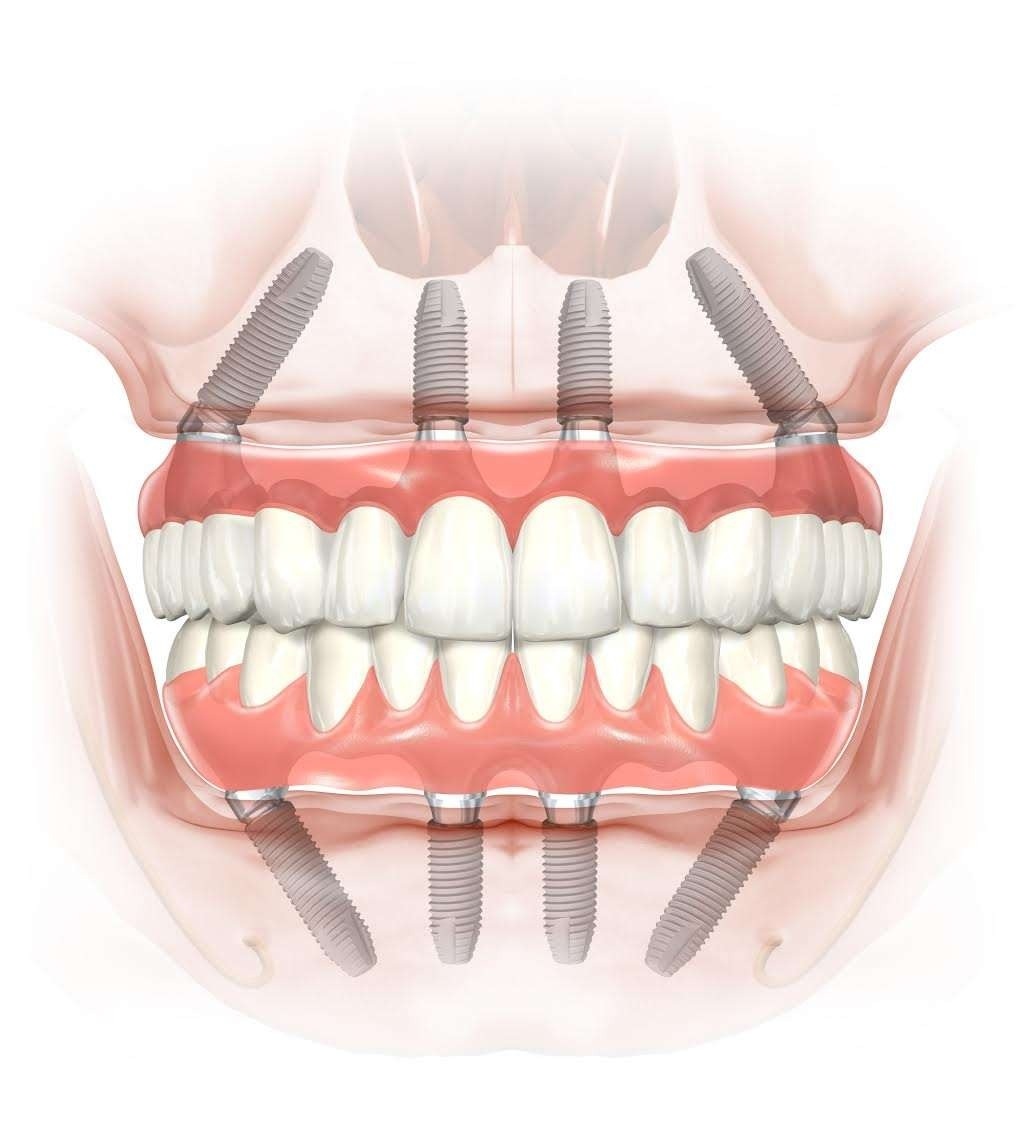

Graftless Full Arch

Best for multiple missing teeth or loose dentures. We place implants in stronger bone areas and give fixed teeth for suitable cases. Local anesthesia keeps you comfortable during treatment.

Get dental implants even with low bone. Advanced techniques avoid bone grafting and reduce treatment time.

Get fixed teeth without bone grafting in suitable cases. Simple plan. Comfortable procedure. Clear recovery.

Best for multiple missing teeth or loose dentures. We place implants in stronger bone areas and give fixed teeth for suitable cases. Local anesthesia keeps you comfortable during treatment.

Many patients think they must do bone grafting first. Some cases can avoid that with graftless implants. You get a safety first plan, comfort focused treatment, and a clear timeline. Every case is different, so we confirm suitability with a 3D scan before treatment.